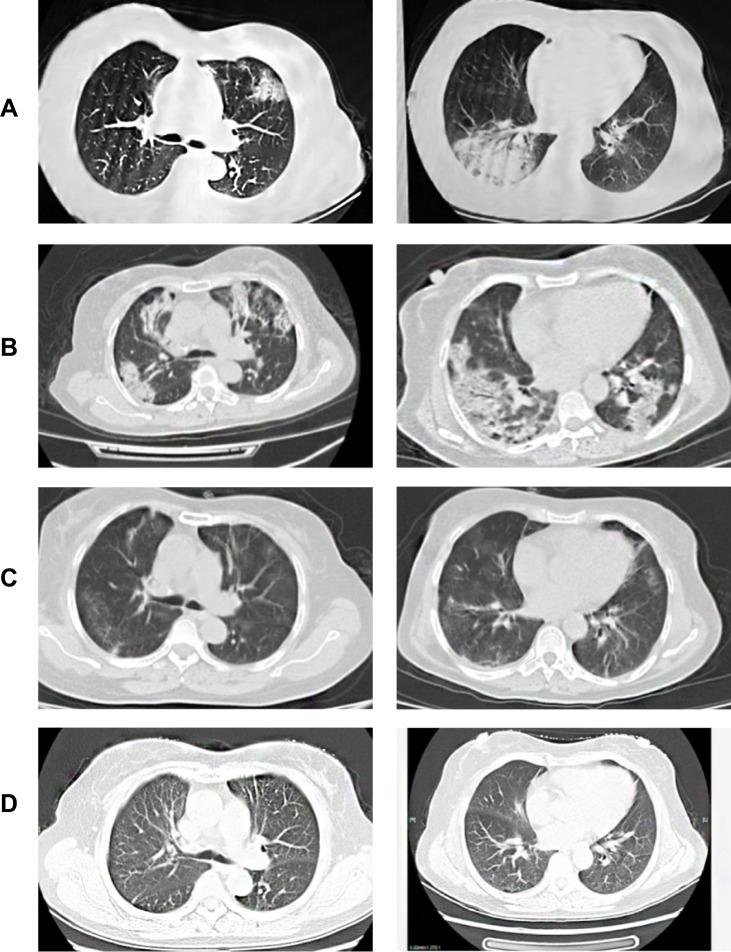

CASE DESCRIPTION

A case of a COVID-19 patient is described and the clinical characteristics are observed as the mildly symptomatic patient progresses into a critically ill patient and during their dramatic improvement with corticosteroid therapy in the early stage of the deterioration process with COVID-19 pneumonia.

描述了一例COVID-19患者的病例,并观察了该轻度症状患者在进展为危重症患者过程中的临床特征,以及在COVID-19肺炎恶化早期接受皮质类固醇治疗后显著改善的过程。